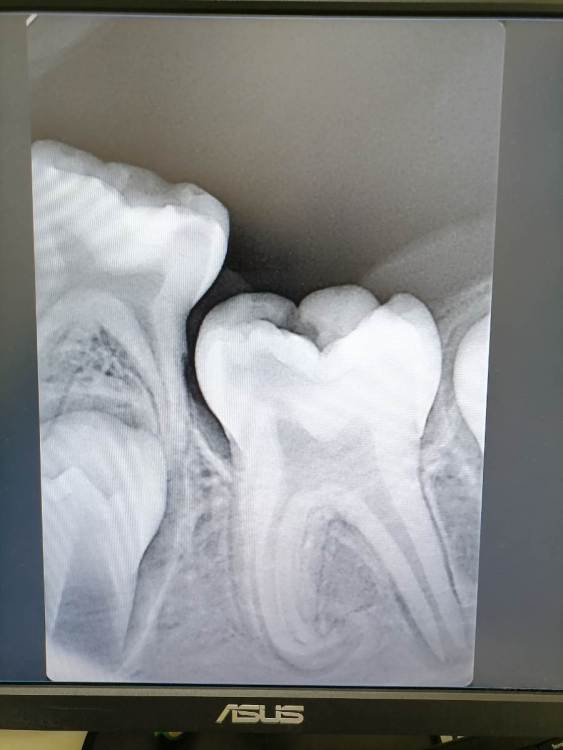

Добрый день. У ребёнка 7 лет пульпит нижней постоянной шестёрки, зуб только прорезался, он ещё в десне, а уже пульпит, упирается в молочную пятёрку. Один стоматолог предлагает удалить молочную пятёрку (чтобы был доступ к шестёрке, так как зуб ещё в десне) , лечить шестёрку, под седацией, так ребёнок не контактный. Другой стоматолог говорит, что лучше эту шестёрку удалить, толку от него уже не будет, IMG_20230323_154612.thumb.jpg.7aac8399e601ec514bbb9fefb6ee3047.jpgна его место встанет будущая семёрка. Как лучше?

Здравствуйте,

интересный случай, на который однозначно  не ответить, так как мало информации

В целом первая мысль - сохранить 6ку , поэтому лечить, скорее всего не в седации , а в мед мне (наркоз)

Но я могу поменять мнение, при получении больше информации)

Нужны: фото в полости рта, как минимум панорамный снимок (ОПТГ), мнение ортодонта, эндодонтиста